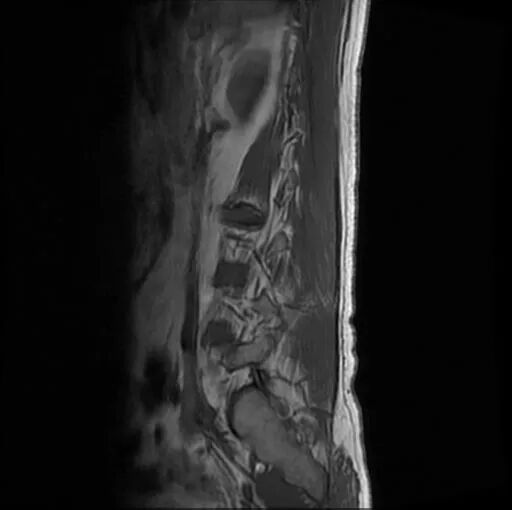

術(shù)前影像資料

圖3:術(shù)前MRI

?